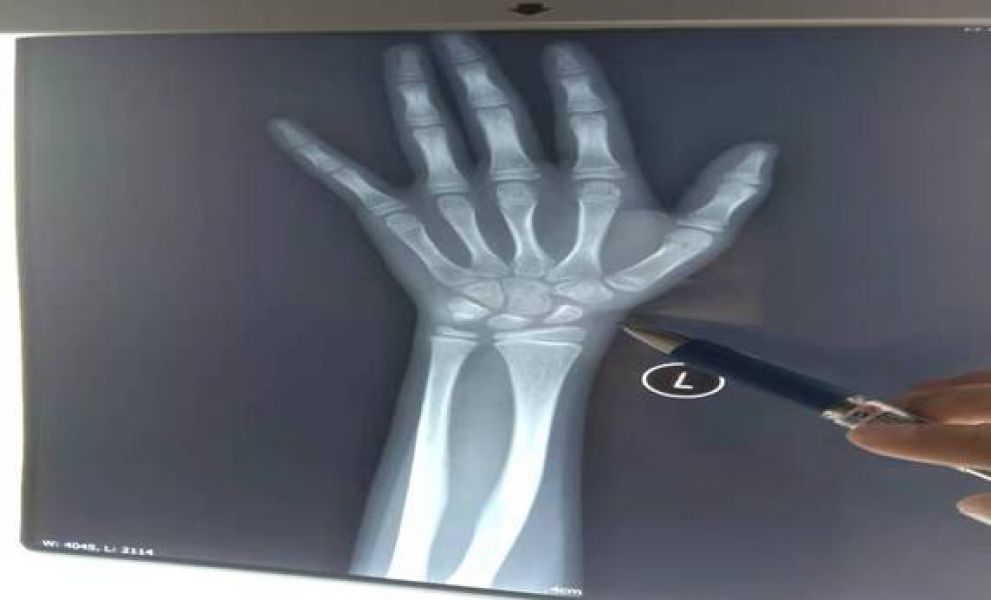

与放射科开展骨龄评定新业务,为矮小症、性早熟等生长发育相关疾病的诊断及治疗打下基础